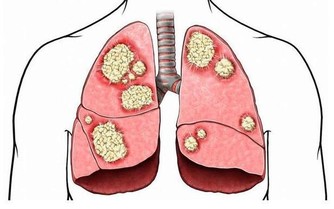

然而,當內臟脂肪堆積過多時,一方面就會形成水

桶腰、將軍肚等造成身材不美觀的問題;另一方面,內臟長期堆積過多脂肪會影響消化功能,

導致內分泌紊亂,還增加了患高血脂、高血壓、脂肪肝等疾病的機會,